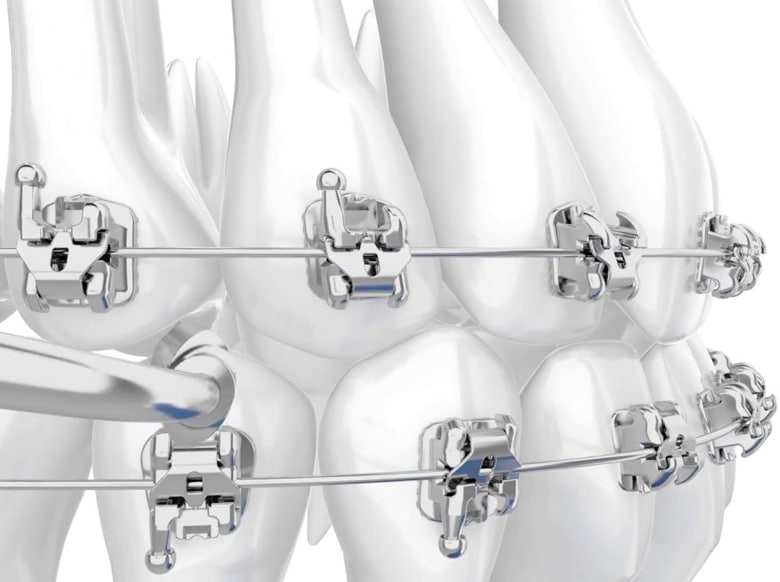

Braketler dişlerin üzerine yapıştırılan ve içerisinden tel geçerek dişlere kuvvet uygulanmasına yarayan aygıtlardır. Tedavi başlangıcında dişlerin üzerine özel yapıştırıcılar ile yapıştırılırlar ve tedavi sonuna kadar sabit olarak dişlerin üzerinde kalırlar. Üretildiği malzemeye göre çeşitli braketler bulunmaktadır.

Kapaklı Braketler

Metal ya da estetik braketler üzerinde özel kapaklı bir mekanizma bulunur şekilde üretilirler. Bu kapaklı mekanizma sayesinde standart braketlerde kullanılan lastik ya da tel ligatür kullanımına gerek olmaz, tel ile braket arasındaki sürtünme kuvveti oldukça azalır ve daha hızlı diş hareketi görülür. Tedavi süresini kısaltmasının yanı sıra, temizlik ve konfor olarak avantajlıdırlar.